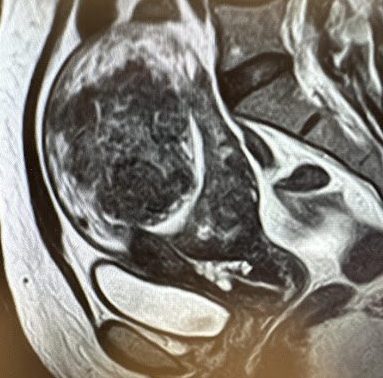

48 year-old female with heavy bleeding and bloating.

MRI showing a large uterus with a dominant 7.5 cm.